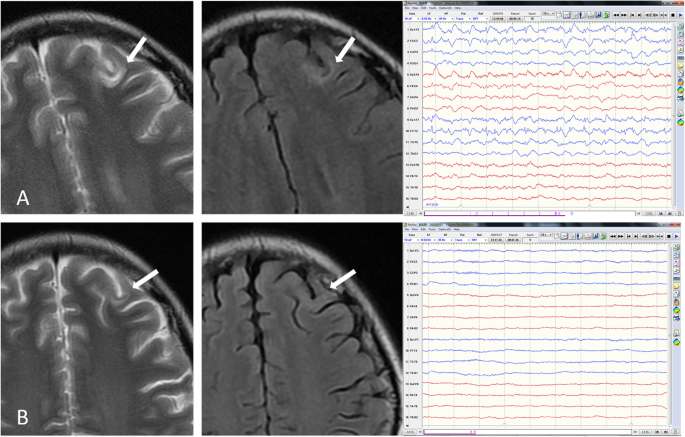

Brain MRI and EEG before and after treatment. Before treatment, T2WI and FLAIR (a, left and middle) showed a left frontal juxtacortical high signal intensity (upper arrows). EEG (a, right) revealed continuous 1.5 Hz spike wave complexes over the left frontal lobe. One month after admission, the lesion became faint on T2WI (b, left, arrow) and nearly undiscernible on FLAIR (B, middle, arrow). EEG (b, right) showed normal electrical activity

A 16-year-old girl presented to the emergency room with status epilepticus which was preceded by 10-day-long period of recurrent seizures. Ten days ago, she began to suffer from recurrent jerky movements in the right arm which sometimes evolved to generalized clonic-tonic seizures. Frequency and duration gradually increased despite the use of levetiracetam 500 mg Q12. Eventually, after the development of status epilepticus, she was sent to the emergency room where intravenous diazepam was injected. When she was transferred to the ward, she was sedated. Brain MRI revealed a left frontal unenhanced juxtacortical demyelinating lesion (Fig. 1 a, left and middle). EEG showed left frontal continuous epileptiform activities (Fig. 1a, right). Intravenous diazepam was tapered off and oral levetiracetam 1000 mg Q12 were prescribed. We also considered lesion resection if the seizures could not be controlled. On day 3, seizures stopped, but the patient was found to be irritable, aggressive and labile. Levetiracetam was replaced by oxcarbazepine 600 mg Q12 and Depakin 500 mg Q12 to reduce side effects. Nevertheless, her mental status continued to worsen. On day 7 she developed delirium, hallucination, delusion, insomnia, oromandibular dystonia, and bradykinesia.

On physical examination, she was agitated, mute and uncooperative. Neurological examination highlighted bradykinesia, nystagmus on lateral gaze, jaw-opening dystonia, difficulty in sticking out tongue, cogwheel rigidity in limbs and shuffling gait. Cerebrospinal fluid (CSF) analysis after lumbar puncture showed normal protein and glucose level but leukocytes were elevated to 17 × 10^6/L. Next generation sequencing for pathogen in CSF was unremarkable. NMDAR-antibody was positive in both serum and CSF samples (diluted 1:100) by cell-based assay (CBA). LGI1, CASPR2, AMPA1, AMPA2, GABAB, DPPX, IgLON5, AQP4, MOG and GFAP were all negative. CSF oligoclonal band was absent. Ovary teratoma was not detected by B-mode ultrasound. A repeat EEG showed diffuse beta waves without previous left frontal epileptiform activities. Anti-NMDA receptor encephalitis was considered. She was started on intravenous methylprednisone of 500 mg daily for 5 days and tapered. Two rounds of IV immunoglobulin (0.4 g/kg/d × 5 days) were used. Her mental status gradually stabilized. Furthermore, dystonia and bradykinesia decreased. On day 30, brain MRI revealed a faint left frontal juxtacortical lesion (Fig. 1b, left and middle). No other abnormalities were observed. EEG showed no epileptiform activities (Fig. 1b, right). On day 43, she was discharged with moderate dystonia. Thirty days after discharge, all the symptoms had resolved. She had no memory of the disease. The demyelinating lesion was even fainter on MRI and EEG showed normal result.